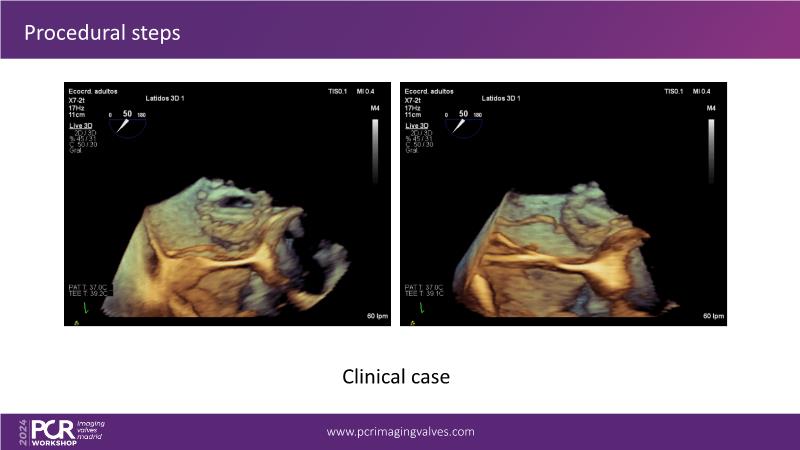

Explore cutting-edge transcatheter valve interventions for mitral and aortic valve disorders, including valve-in-valve procedures and management strategies for paravalvular leakages, and learn about diagnosing and treating mitral annular calcification and transcatheter options in infective endocarditis.

- To get tips and tricks for guidance of transcatheter intervention